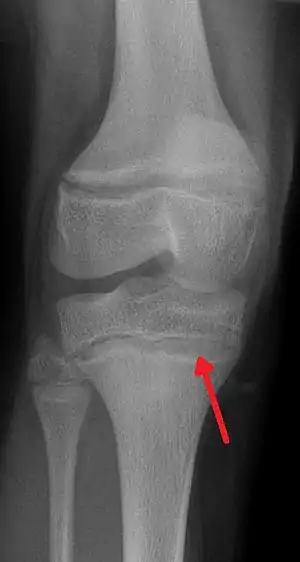

| An X ray demonstrating the characteristic finding of lead poisoning in humans—dense metaphyseal lines. | |

Exposure to lead can occur by contaminated air, water, dust, food, or consumer products.[2] Children are at greater risk as they are more likely to put objects in their mouth such as those that contain lead paint and absorb a greater proportion of the lead that they eat.[2] Exposure at work is a common cause of lead poisoning in adults with certain occupations at particular risk.[7] Diagnosis is typically by measurement of the blood lead level.[2] The Centers for Disease Control (US) has set the upper limit for blood lead for adults at 10 µg/dl (10 µg/100 g) and for children at 5 µg/dl.[8][9] Elevated lead may also be detected by changes in red blood cells or dense lines in the bones of children as seen on X-ray.[4]

Blood lead levels are an indicator mainly of recent or current lead exposure, not of total body burden.[171] Lead in bones can be measured noninvasively by X-ray fluorescence; this may be the best measure of cumulative exposure and total body burden.[21] However this method is not widely available and is mainly used for research rather than routine diagnosis.[85] Another radiographic sign of elevated lead levels is the presence of radiodense lines called lead lines at the metaphysis in the long bones of growing children, especially around the knees.[172] These lead lines, caused by increased calcification due to disrupted metabolism in the growing bones, become wider as the duration of lead exposure increases.[172] X-rays may also reveal lead-containing foreign materials such as paint chips in the gastrointestinal tract.[16][172]